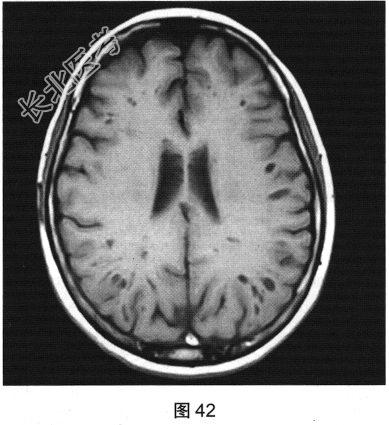

- [材料题] 患者女性,56岁,诉头痛、头晕多年,要求行颅脑MRI检查。查体:神志清楚,问答切题,查体合作。双眼睑无水肿、下垂及闭合不全,双侧瞳孔直径约3.0mm,直接、间接反射均灵敏。双眼视力视野粗侧无异常。发音清晰无嘶哑。耸肩及转头力量对称。四肢活动灵活,肌力、肌张力正常,深浅感觉基本正常;病理征阴性。患者行颅脑MRI检查,如图41~图44所示。

- 多项选择题2.[提示]患者行FLAIR、DWI及增强扫描,见图45~图54。该患者MRI影像的主要阳性表现有( )

C、双侧放射冠及半卵圆中心多发条状、圆形及卵圆形异常信号灶

E、病灶呈长T1、长T2信号,FLAIR为低信号,DWI为低信号,ADC为高信号